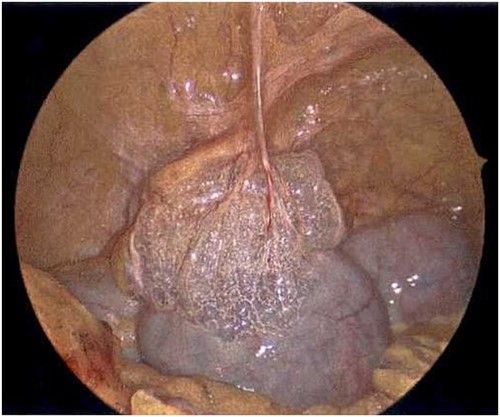

On Hospital Day 2, an interval CXR showed continued resolution of the right-sided pneumothorax but worsening subcutaneous emphysema of the bilateral chest wall and pneumoperitoneum (Fig. 3). Surgical consultation was sought, leading to diagnostic laparoscopy. In the abdomen, emphysematous changes within the gastrohepatic ligament and omental adhesions to the anterior abdominal wall were visualized (Figs 5 and 6). Laparoscopic exploration revealed no diaphragmatic injury or perforated viscera but identified emphysematous changes throughout the preperitoneal space, small and large bowel mesentery, and right paracolic gutter (Figs 7 and 8). Immediate post-op CXR no longer showed evidence of pneumoperitoneum (Fig. 4). The patient was transferred back to the ICU and extubated after three days on Day 5. After the removal of chest tube and transfer to a medical floor on Day 8, the patient developed aspiration pneumonia that was treated with antibiotics. She was discharged on Day 15.

Laparoscope revealing emphysematous changes within the gastrohepatic ligament.